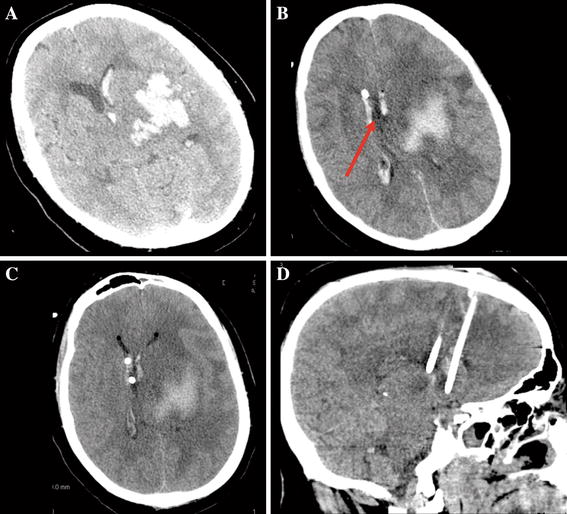

From www.semanticscholar.org

Figure 1 from SAFETY AND ACCURACY OF BEDSIDE EXTERNAL VENTRICULAR DRAIN Bedside Ventriculostomy Among critically ill patients, the procedure is usually performed at the bedside. An evd is the gold standard approach to measurement of intracranial pressure, because it allows for. Bedside ventriculostomy is a safe and accurate procedure for intracranial pressure monitoring and cerebrospinal fluid drainage. Typically placed at the bedside by a neurosurgeon or neurointensivist using surface landmarks under emergent conditions,. Bedside Ventriculostomy.

From www.mdpi.com

Diagnostics Free FullText Power Drill Craniostomy for Bedside Bedside Ventriculostomy An evd is the gold standard approach to measurement of intracranial pressure, because it allows for. Bedside ventriculostomy is a safe and accurate procedure for intracranial pressure monitoring and cerebrospinal fluid drainage. 29088962), length of time catheter is in place is a risk factor. Among critically ill patients, the procedure is usually performed at the bedside. Evd placement is one. Bedside Ventriculostomy.